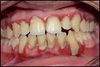

Avant: Gencive Enflammée

Après: Gencive dégonflée et stabilisée

après 6 semaines de brossage